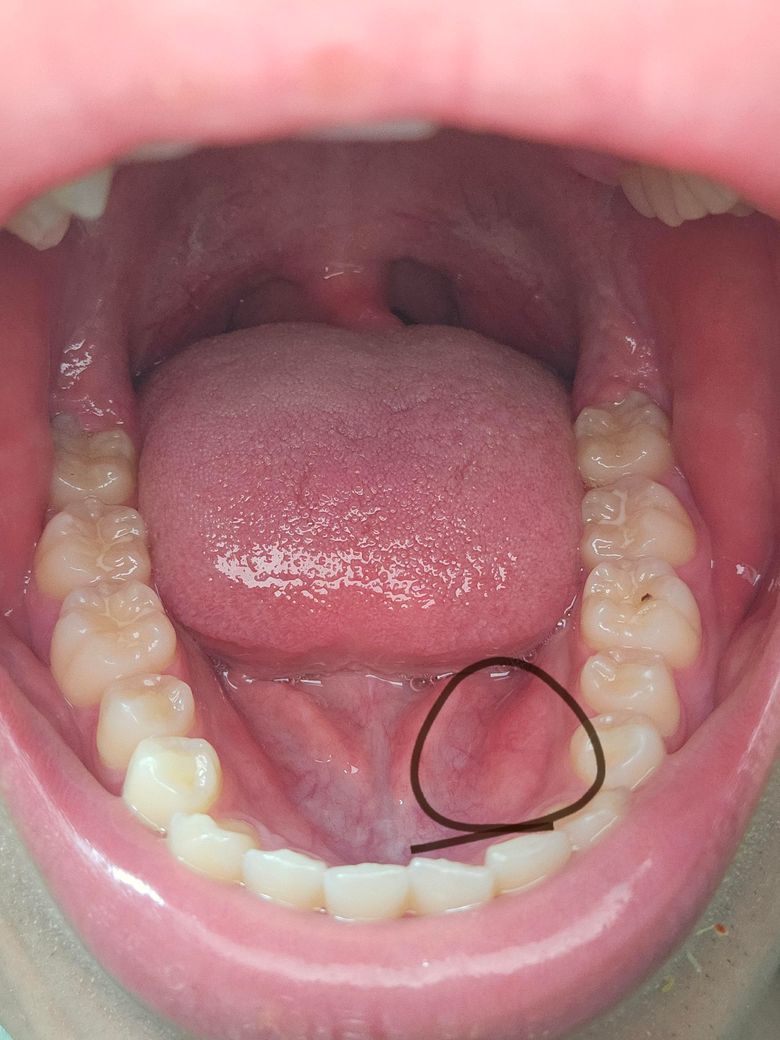

맞습니다. 아래쪽 사진중에 튀어나온 뼈가 하악골 융기라고 불리는 해부학적 구조가 맞습니다.

딱딱하다면 골융기가 맞습니다.

저정도는 작은 편입니다. 불편하지 않으면 신경쓰지 마시고 생활하시면 되겠습니다.

하악 골융기는 딱딱한 뼈의 돌출이며, 대부분의 경우 통증이 없습니다. 골융기는 대부분 치료가 필요하지 않으나 만약 통증이나 불편감이 있는 경우에는 치과 진료를 받길 권합니다.

하악골 융기가 맞으며 하악골 융기는 특별히 치료를 하지 않아도 되며 그냥 지내시면 됩니다.

사진으로만 봤을 경우에는 골 융기가 맞은 것으로 보입니다 골 윤기는 특별한 문제를 발생시키지 않기 때문에 내버려둬도 됩니다 딱딱한 음식을 먹게 되면 해당 부위에 상처가 날 수 있으니 너무 딱딱한 음식을 덜 먹는 것이 좋습니다

위치상, 아주 딱딱하게 느껴진다면 하악골융기(mandibular torus)가 맞을 것으로 예상됩니다. 그냥 정상 뼈 구조이고요. 걱정하지 않아도 됩니다. 추후 틀니를 하게 될 경우 해당 부위가 틀니에 눌려서 아플 수 있는데 그렇다고 지금 제거할 필요는 없습니다.